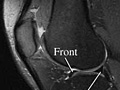

Magnetic resonance imaging (MRI) is a test done with a large machine that uses a magnetic field and pulses of radio wave energy to make pictures of the knee. Muscles, ligaments, cartilage, and other joint structures are often best seen with an MRI. In many cases an MRI gives information about structures in the body that cannot be seen as well with an X-ray, ultrasound, or CT scan.

For an MRI test, you are placed inside the magnet so that your knee is inside the strong magnetic field. An MRI can find changes in the structure of organs or other tissues. It also can find tissue damage or disease, such as infection or a tumor. Pictures from an MRI scan are digital images that can be saved and stored on a computer for further study. The images also can be reviewed remotely, such as in a clinic or an operating room. Photographs or films of selected pictures can also be made.